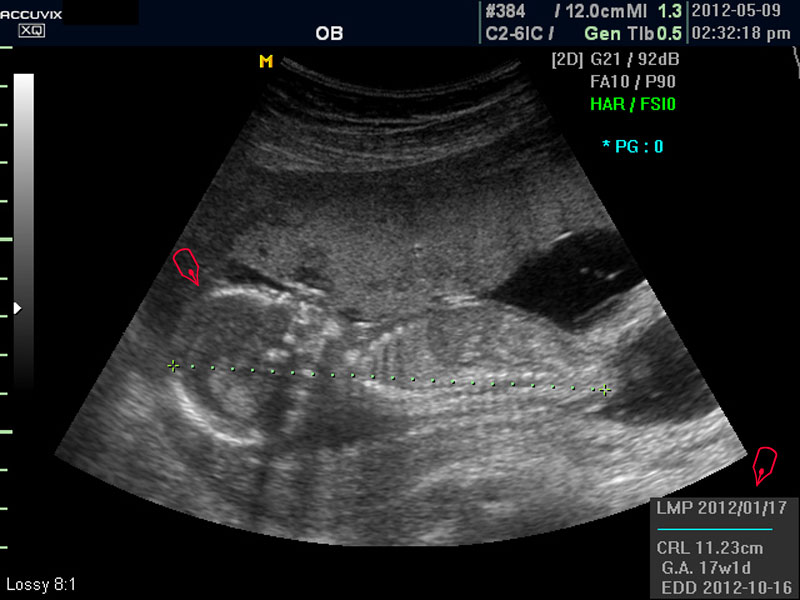

우선 초음파 사진에서 볼 것은 태아의 크기가 정상인가 하는 것입니다.

보통 태아의 발육은 머리부터 엉덩이까지의 크기인 CRL(Crown Rump Length의 약자)이 정상인가 하는 것과 태아의 두상 크기인 BPD(BiParietal Diameter의 약자)가 정상 범위에 들어 있는가 하는 것으로 판단합니다.

모든 사진에서 우측 하단에는 기본적인 발육 정보가 기록되는데 세번째 사진에서 빨간 펜으로 표시한 부분이며 그 내용의 의미는 아래와 같습니다.

참고로 이런 측정 수치가 나타나는 양식이나 위치는 초음파 장비마다 다르지만 용어는 대체로 공통된 의학 용어를 사용하기 때문에 대동소이합니다.

1. LMP

Last Menstrual Period의 약자로 최종 월경일입니다. 이런 최종 월경일을 바탕으로 현재의 임신 주수와 초음파상 측정 지표들간에 얼마나 괴리 되어 있나 하는 것을 판단하는 것입니다.

2. CRL

위에 말한 태아 크기를 말하는 지표로 실제 수치가 표시됩니다.

3. GA

Gestational Age의 약자로 우리말로는 임신 주기라고 하며 CRL이나 BPD등을 기준으로 했을때 임신 몇주 며칠에 해당하는 지 나타낸 것입니다.

5.EDD

Estimated Due Date의 약자로 초음파 측정치를 바탕으로 산출한 출산 예정일입니다.